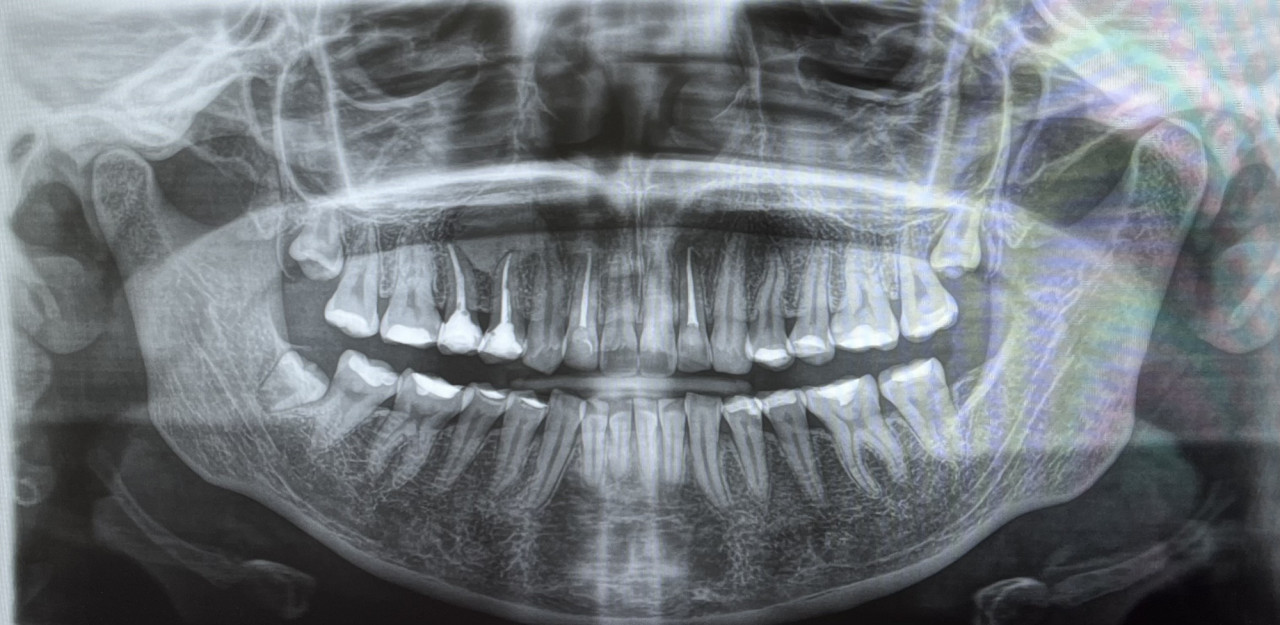

нужно ли будет удалять зубы мудрости для брекет системы, если ортодонт сказал, что "иногда" он не отправляет на удаление.

И что такое может быть серое пятно около корня зуба(если мне не кажется) , надеюсь очень что не киста......

Здравствуйте. По этому панорамному снимку заранее сказать, что зубы мудрости точно нужно удалять нельзя и решение зависит от плана ортодонтического лечения и наличия места в зубном ряду. Часто мудрости удаляют при скученности, но если места хватает и они не давят на соседние зубы, их могут оставить.

Серое пятно у корня на снимке может быть проекционной тенью, особенностью качества снимка или анатомической структурой. Киста на таком изображении обычно выглядит чётко и округло. Чтобы точно исключить патологию, стоит сделать прицельный снимок или КТ у стоматолога.